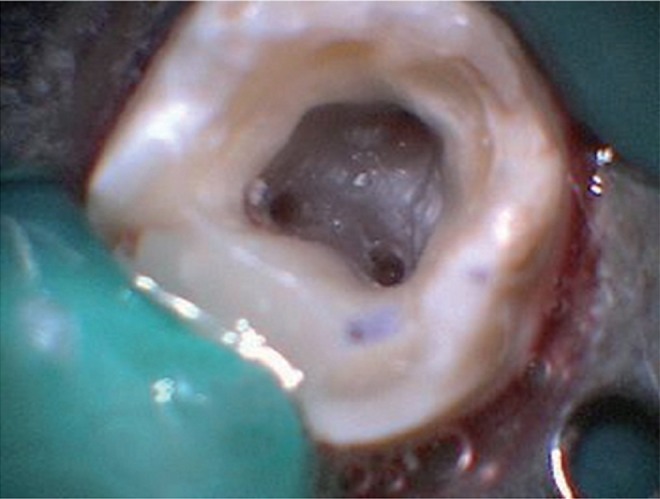

Radiographic evaluation of the involved tooth revealed an unusual anatomical configuration suggesting the possibility of the presence of two mesial roots (Figure 1a). The mesial surface of the tooth was restored with composite resin (P60, 3M ESPE, St. Paul, MN, USA) after caries excavation to enable optimal isolation. The tooth was anesthetized using 1.8 mL 2% lidocaine with 1 : 200,000 epinephrine (Xylocaine, AstraZeneca Pharma India Ltd., Bangalore, India). Following rubber dam isolation, an endodontic access cavity was established. On inspection with a DG-16 endodontic explorer (Hu-Friedy, Chicago, IL, USA) under an operating microscope (Roslane Meditech, Haryana, India), the pulp chamber floor revealed three canal openings corresponding to the two mesial and one distal roots (Figure 2). The mesiobuccal, mesiolingual, and distal canal orifices were located in their regular locations at the angles in the floor-wall junction. Further inspection of the pulpal floor was done for search of other orifices that were absent. Coronal enlargement was done with a nickel-titanium (NiTi) ProTaper SX rotary file (Dentsply Maillefer) to improve the straight-line access. The pulp tissue was extirpated using barbed broaches (Dentsply Tulsa, Tulsa, OK, USA). The working length was initially determined with the help of an apex locator (Raypex5, VDW, Munich, Germany) and confirmed using radiographs taken at different horizontal angulations. The working length radiographs showed three independent root canals in three separated roots (Figure 1b). Cleaning and shaping was done using ProTaper NiTi rotary instruments (Dentsply Maillefer) along with ethylenediaminetetraacetic acid (Glyde File Prep, Dentsply Tulsa) using a crown-down technique. Irrigation was performed using 3% sodium hypochlorite solution (Cmident, Cmident, New Delhi, India). Afterwards, a closed dressing was given with a sterilized cotton pellet in the pulp chamber with access cavity restored with Cavit G (3M ESPE).

Unusual occurrence of an extra mesial root has significant implications in clinical dentistry. During the endodontic treatment, modification in the access cavity design is usually a common landmark for teeth having accessory roots, especially when they are well separated with a coronal bifurcation.11,18 The orifice of the additional mesial root is located along the same horizontal line as that of the orifice of the main mesial root. The mesial wall of the access cavity needs to be extended more in a buccolingual direction to locate and gain access to the well separated canal orifices (Figure 2).11 Before initiating the mechanical instrumentation of the root canal, it is important to evaluate the dentine wall thickness and curvature of accessory roots.10,18 This is because the accessory roots are relatively thin and the root canal instrumentation should be performed with caution to avoid perforation or stripping caused by over-enlargement of the encased root canals. Additionally, accessory mesial roots may also present with severe curvatures and narrow canals.10 Therefore, after relocation and enlargement of the canal orifice, initial exploration of the root canal must be done with small files (size 10 or less) followed by creation of a glide path before shaping the canal using flexible nickel titanium hand and rotary files of suitable taper with lubrication. This helps in preserving the normal root canal geometry, and also prevents the incidence of shaping aberrations such as instrument separation, ledge formation, root canal transportation, straightening of the root canal, and loss of working length.18 Furthermore, the presence of third root poses a significant challenge in case of endodontic surgical procedures.19

An intraoral photograph showing the wide buccolingual dimension of the mesial orifices.

Figure 2 An intraoral photograph showing the wide buccolingual dimension of the mesial orifices.